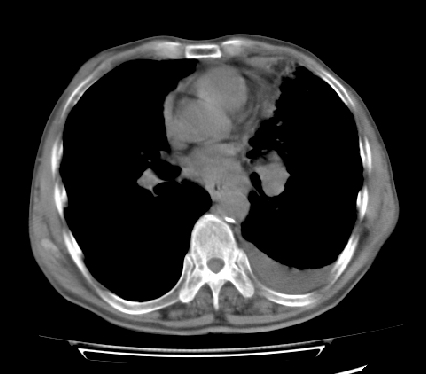

以下是引用ct诊断高手在2009-5-29 13:50:00的发言:[br]考虑左侧中央型肺癌,阻塞性肺炎伴肺不张。纵隔淋巴结转移。慢支 肺间质纤维化肺气肿。左侧胸腔积液。左侧肋骨转移?

以下是引用hhcckk在2009-5-29 14:58:00的发言:[br]左上周围型肺癌,左肺门、纵隔淋巴结转移,左侧胸腔积液,左侧肋骨转移[br]